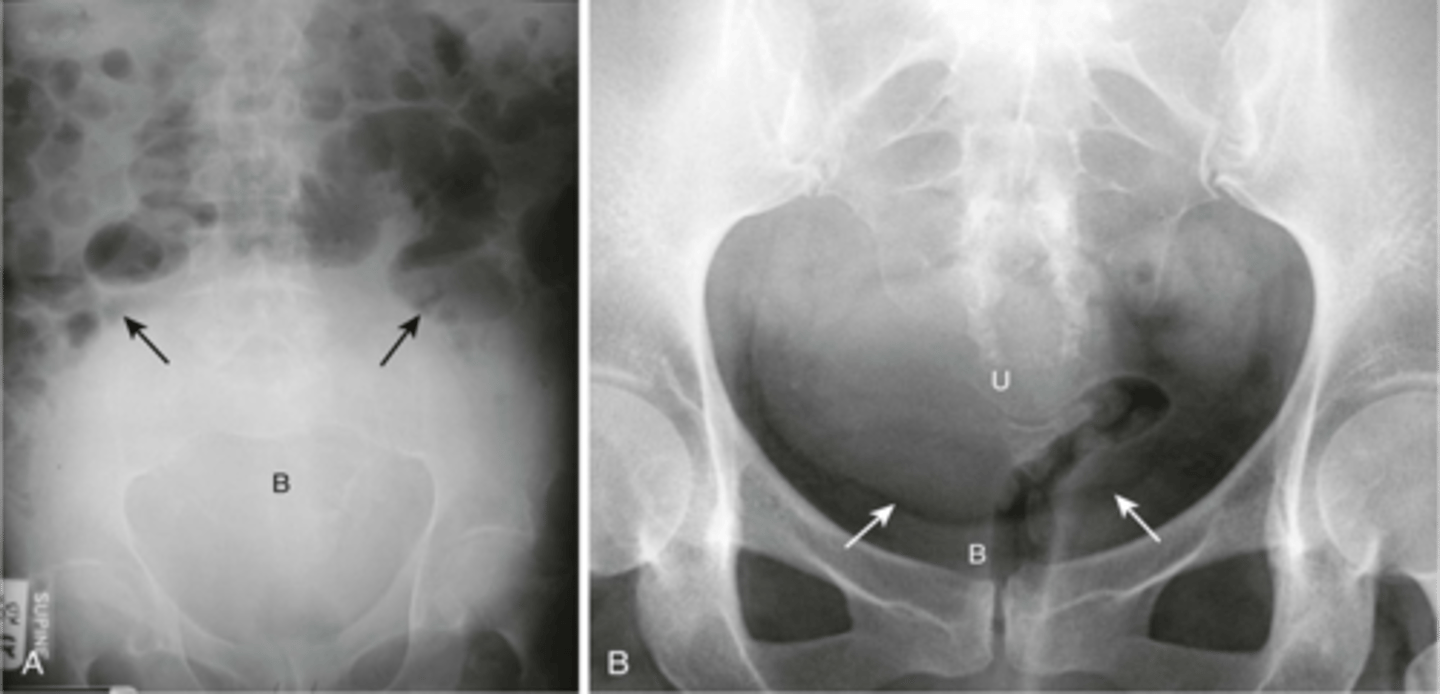

Normal bladder

left: distended bladder

right: enlarged uterus